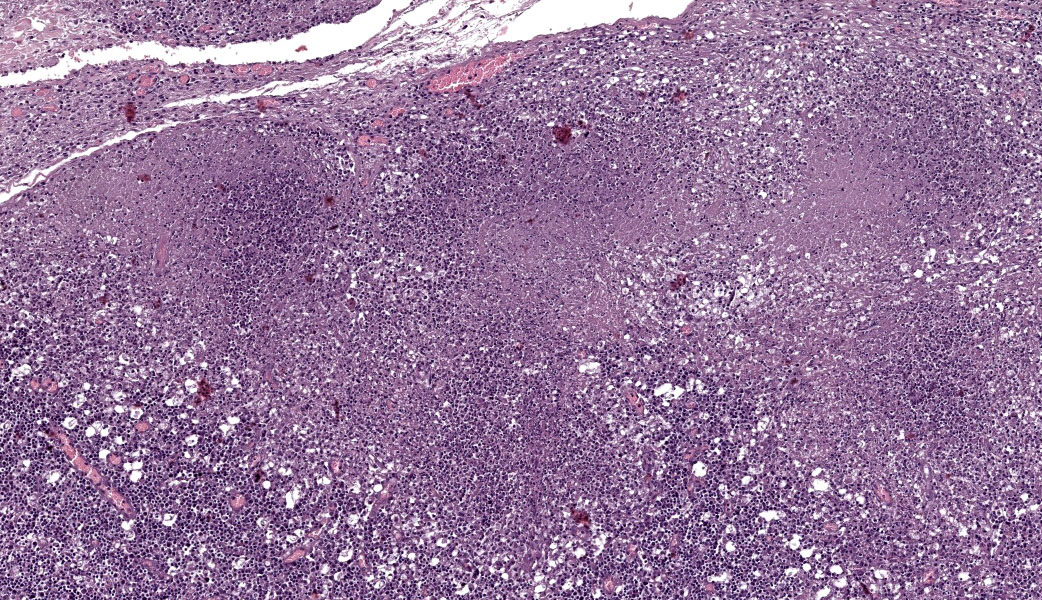

Microscopic Description:

Abdominal lymph node: Multifocal, severe cellular infiltrates with undefined margins are randomly distributed within the lymph node parenchima especially in the subcapsular areas. They extend into the serosal expanding and effacing the mesothelial lining. The infiltrates are characterized by a severe mixed inflammatory population with largenumbers of both viable and lytic neutrophils surrounded by occasional large macrophages with abundant cytoplasm and rare lymphocytes and plasma cells. In the center of almost each infiltrate the neutrophils population shows karyolysis, pyknosis, karyorrhexis and the accumulation of extensive amount of amorphous eosinophilic, proteinaceous material admixed with cellular debris (lytic necrosis).

Lymph node: Lymphadenitis and capsulitis, necrotizing and granulomatous, chronic, multifocal to coalescing, marked, with paracortical hyperplasia.